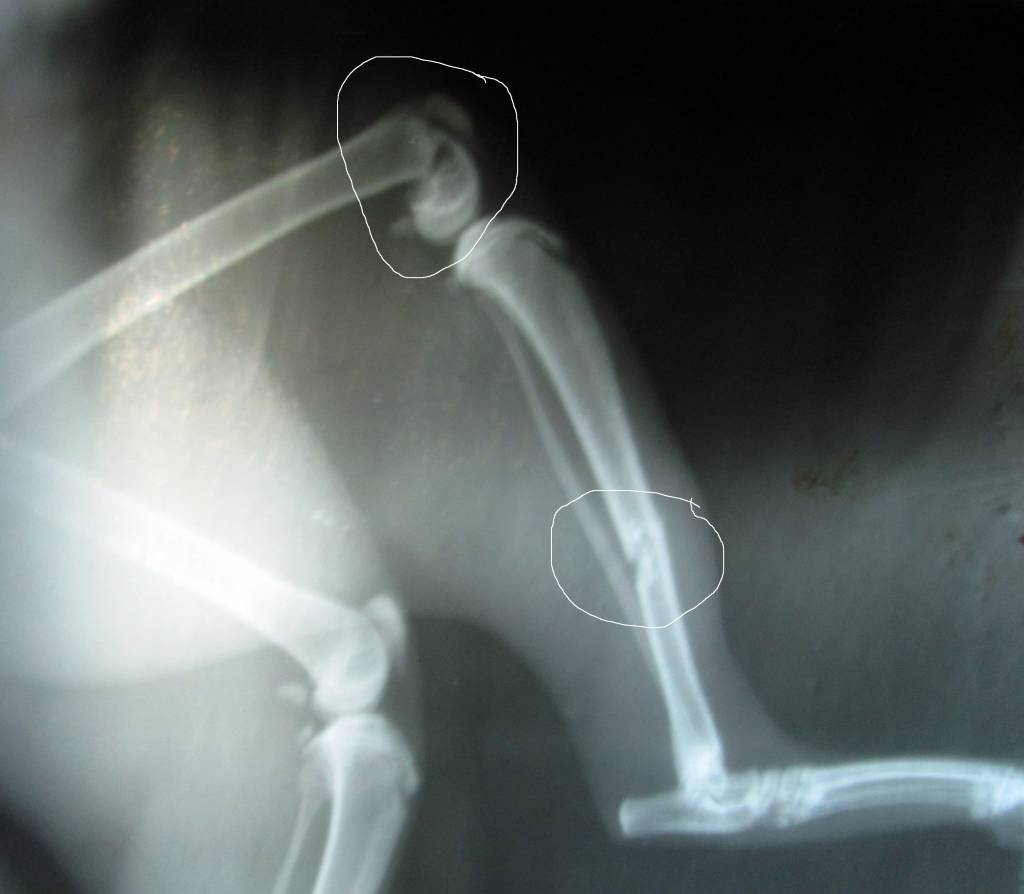

Как-то Мальчишке "ножку" сломали, кости собирали... резали, лечили... чинили...

потихоньку поправился, стал снова ловить птиц...

а через полгода покусали собаки (стая из 5 собак), снова лечились снова резали зашивали... шкура была прокусана-разодрана в 7-8 местах, сломано Два ребра... и Снова ВЫЖИЛИ!!! (это было в январе)

а теперь Вот опять лечимся, говорят что-то вирусное подхватили... пока с катетором в лапе (в вене) ходит... прокапываемся, колемся, лечимся... и ЖДЁМ ЛЕТА!!!